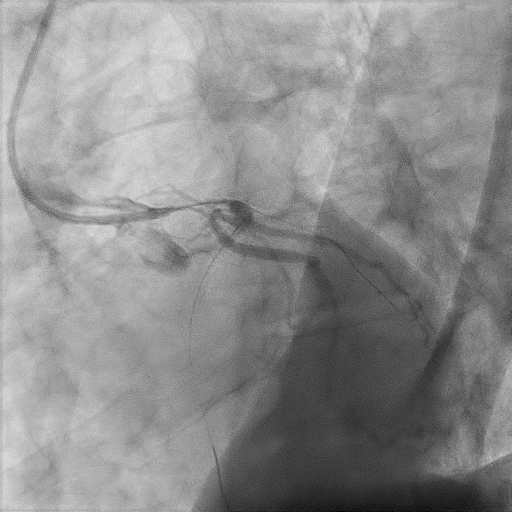

We proceeded with delayed selective PCI to the left anterior descending artery (LAD). The left main coronary artery (LMCA) was engaged with guiding catheter Medtronic Launcher 6FR EBU 3.5. The PTCA guide wire Shun R (SHUNMEI Medical) crossed the lesion with ease. Besides, we wired the diagonal 1 with PT2 (Boston Scientific) to provide side branch protection. The proximal to mid segment of the LAD lesion was pre-dilated with Sapphire NC 24 PTCA balloon 3.0x15mm and inflated to 12 atm. The lesion was stented with Xience Xpedition 3.0x48mm and inflated to 10atm. The stent was post-dilated with NC Trek balloon 3.5x12mm and inflated to 14atm. Noted while retracting the balloon during post-dilatation, the guiding catheter advanced deep into the LMCA several times. Subsequently, patient became progressively hemodynamically unstable. Trial of aspiration with Genoss Extractor but no thrombus was aspirated. Intracoronary Tirofiban bolus was administered. Unfortunately, patient went into cardiorespiratory arrest and intensive resuscitation was commenced. Angiography showed severe flow-limiting type D dissection of the LMCA. We proceeded with rescue stenting of LMCA with Xience Sierra 3.5x38mm with inflation to 12atm. The stent was post-dilated with NC Euphora 4.0x8mm and inflated to 18atm. The final result was TIMI flow 3 but the stent was about 3 to 5 mm proximal to the LMCA ostium. An intra-aortic balloon pump was also inserted and patient required 4 inotropes.

Case Summary